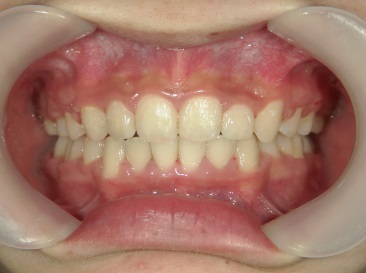

矯正歯科 治療後矯正歯科 全顎ワイヤー矯正 治療後矯正歯科(全顎ワイヤー矯正)治療後

18歳女性 浜松市中区在住

治療期間3年11ヶ月

主訴:上の歯が前に出ている。

矯正歯科 治療前 左右上下4番  計4本抜歯

矯正歯科 治療後

no.18_2196_治療後_右.jpgno.18_2196_治療後_正面.jpgno.18_2196_治療後_左.jpg